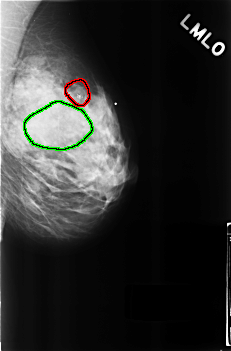

C_0272_1.LEFT_MLO

LEFT_MLO LINES 4560 PIXELS_PER_LINE 2992 BITS_PER_PIXEL 12 RESOLUTION 50 OVERLAY

FILE: C_0272_1.LEFT_MLO.OVERLAY

TOTAL_ABNORMALITIES 2

ABNORMALITY 1

LESION_TYPE CALCIFICATION TYPE AMORPHOUS DISTRIBUTION CLUSTERED

ASSESSMENT 4

SUBTLETY 5

PATHOLOGY BENIGN

TOTAL_OUTLINES 1

BOUNDARY

ABNORMALITY 2

LESION_TYPE MASS SHAPE OVAL MARGINS OBSCURED

ASSESSMENT 3

SUBTLETY 4